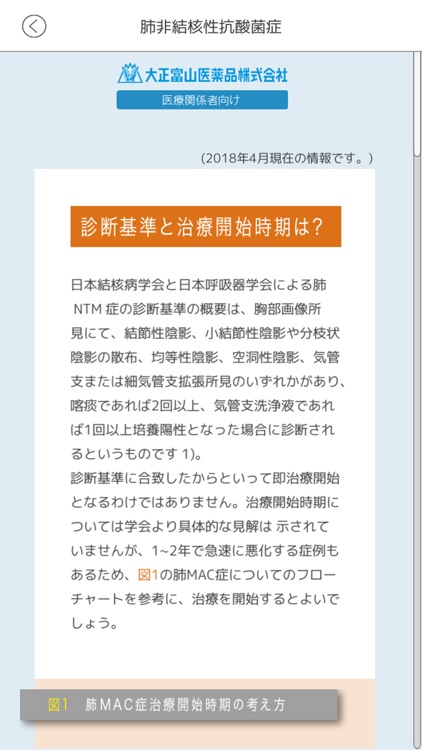

②各疾患の診断・治療において参考となる情報をすぐに参照できます。(画面2)